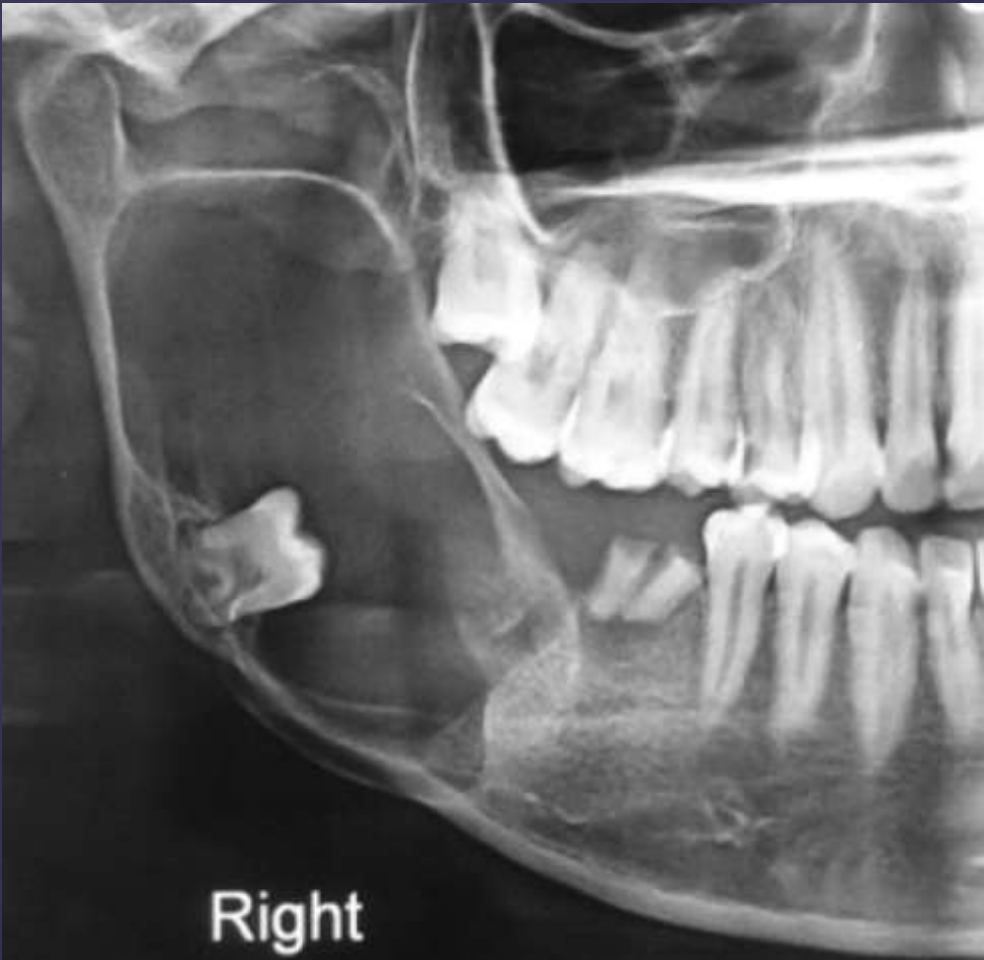

cementoblastomas

external root resorption 30

displacement of IAN canal inferiorly

thinning/expansion of inferior border of mandible